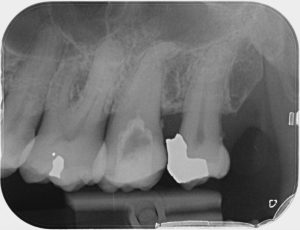

Clinical Cases